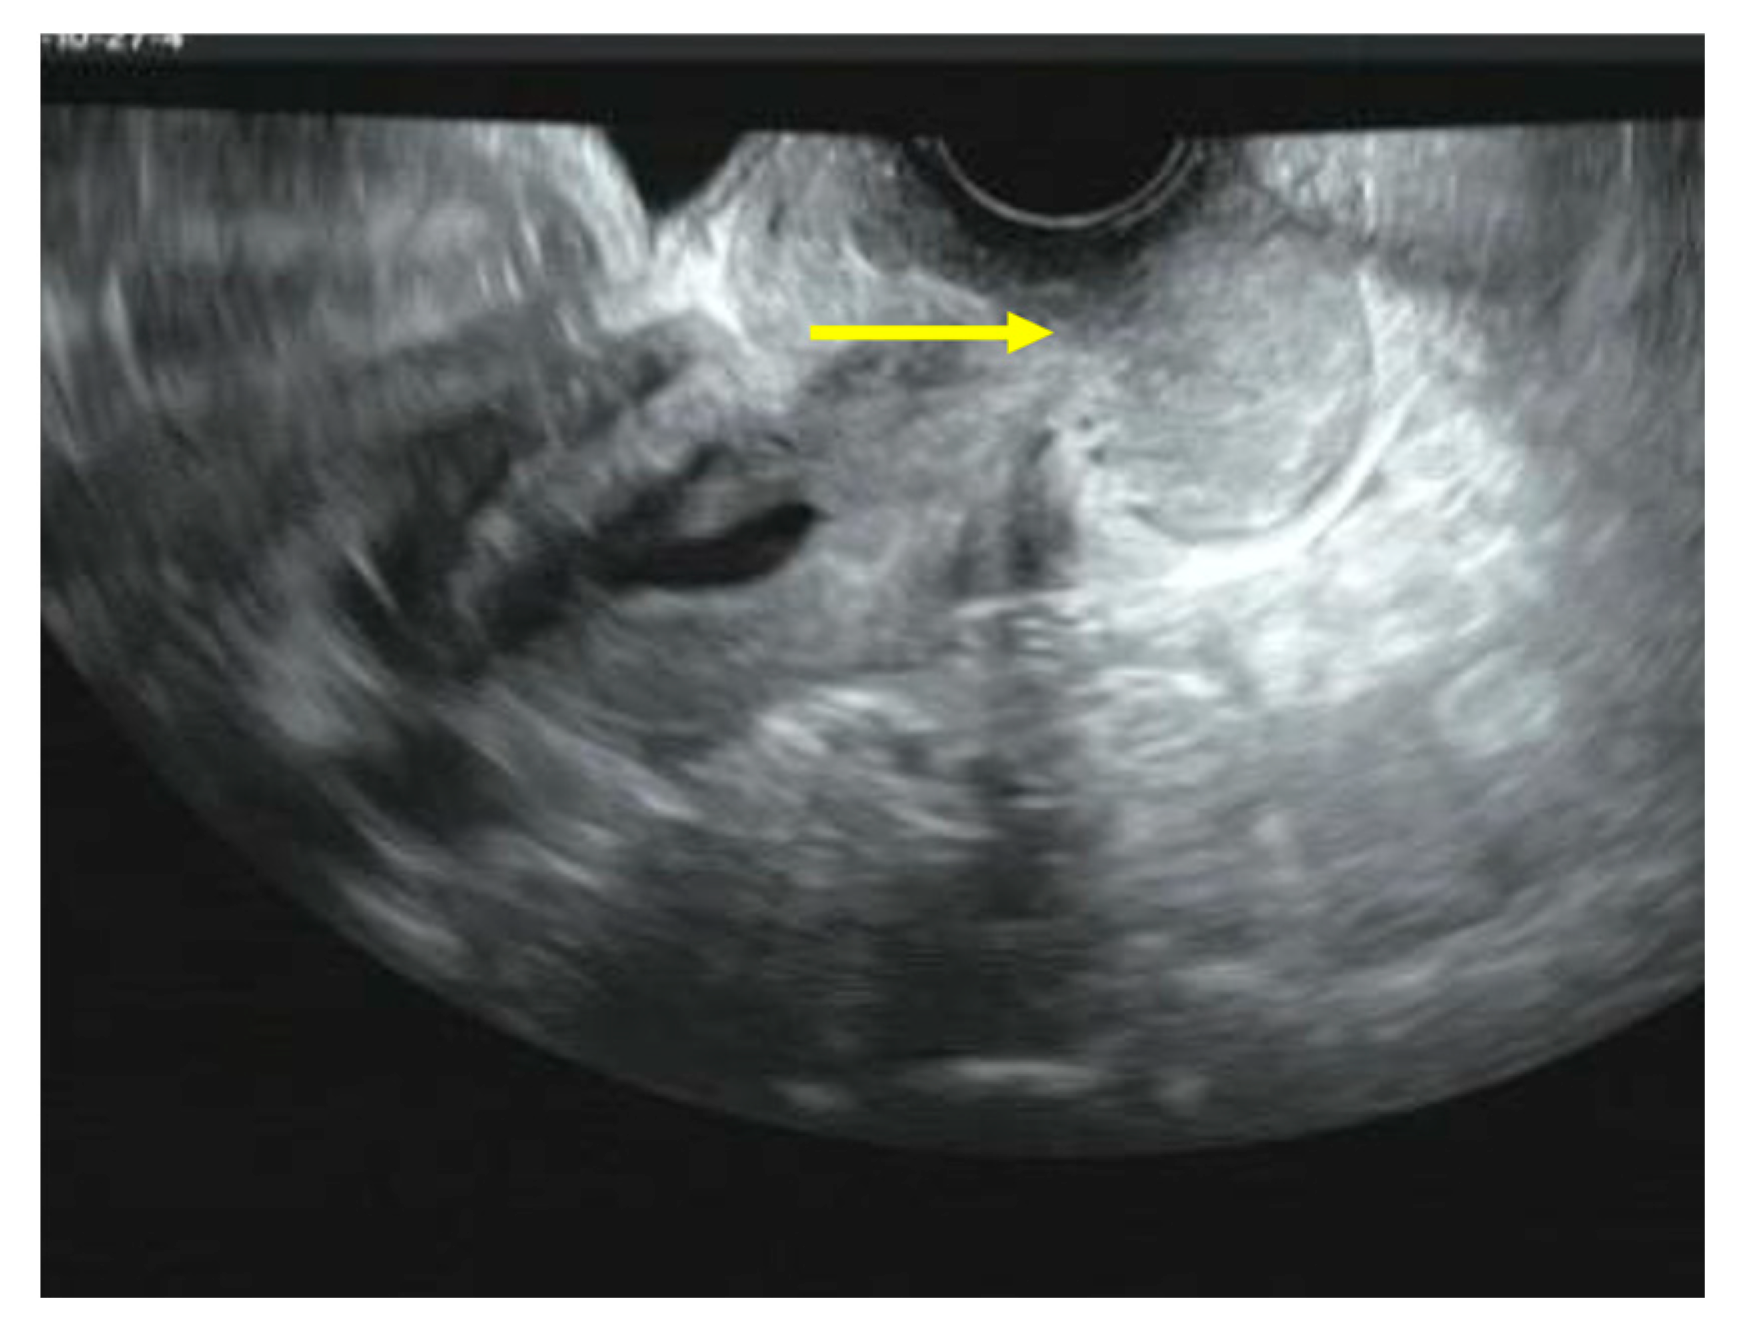

Figure 2.

Transvaginal ultrasound scan. A cervical tumor measuring 47 × 22 mm.